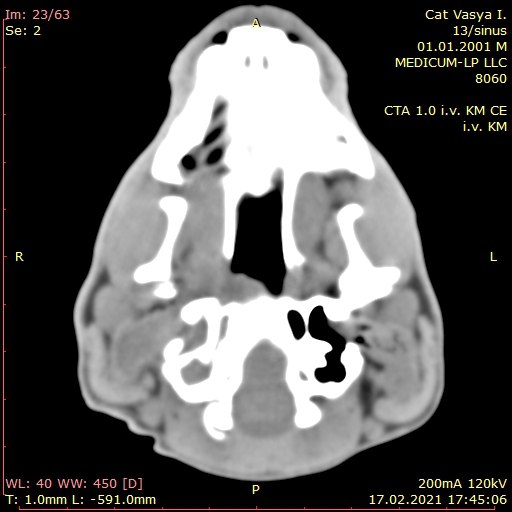

ДОЗВОЛЯЄ ДІАГНОСТУВАТИ:

📌Онкологічні процеси на ранніх стадіях

📌Метастази на ранніх стадіях

📌 Планування оперативного втручання

📌Судинні патології

📌Оцінити кровотік в новоутвореннях

📌Патології хребетного стовпа і суглобів